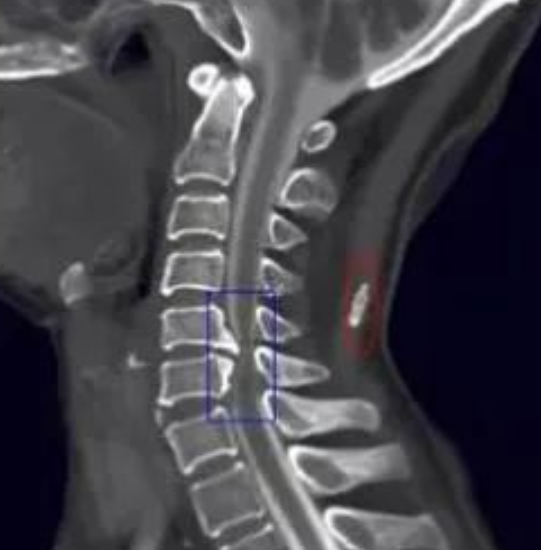

找到这些影像征象,复杂的骨肿瘤迎刃而解

骨肿瘤的基本影像学征象是构成骨肿瘤最基本的元素,无论多复杂的骨肿瘤都由一个或几个基本影像学征象构成,对其透彻理解和准确把握是正确诊断骨肿瘤的重要前提。